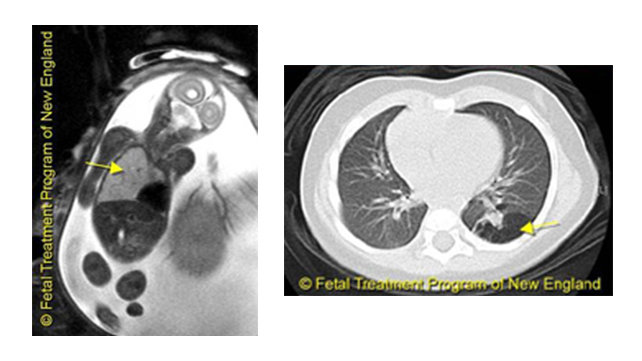

Before birth, they are diagnosed through ultrasound and fetal magnetic resonance imaging (MRI). They can also be discovered accidentally, on a chest x-ray, later in childhood or even adulthood.